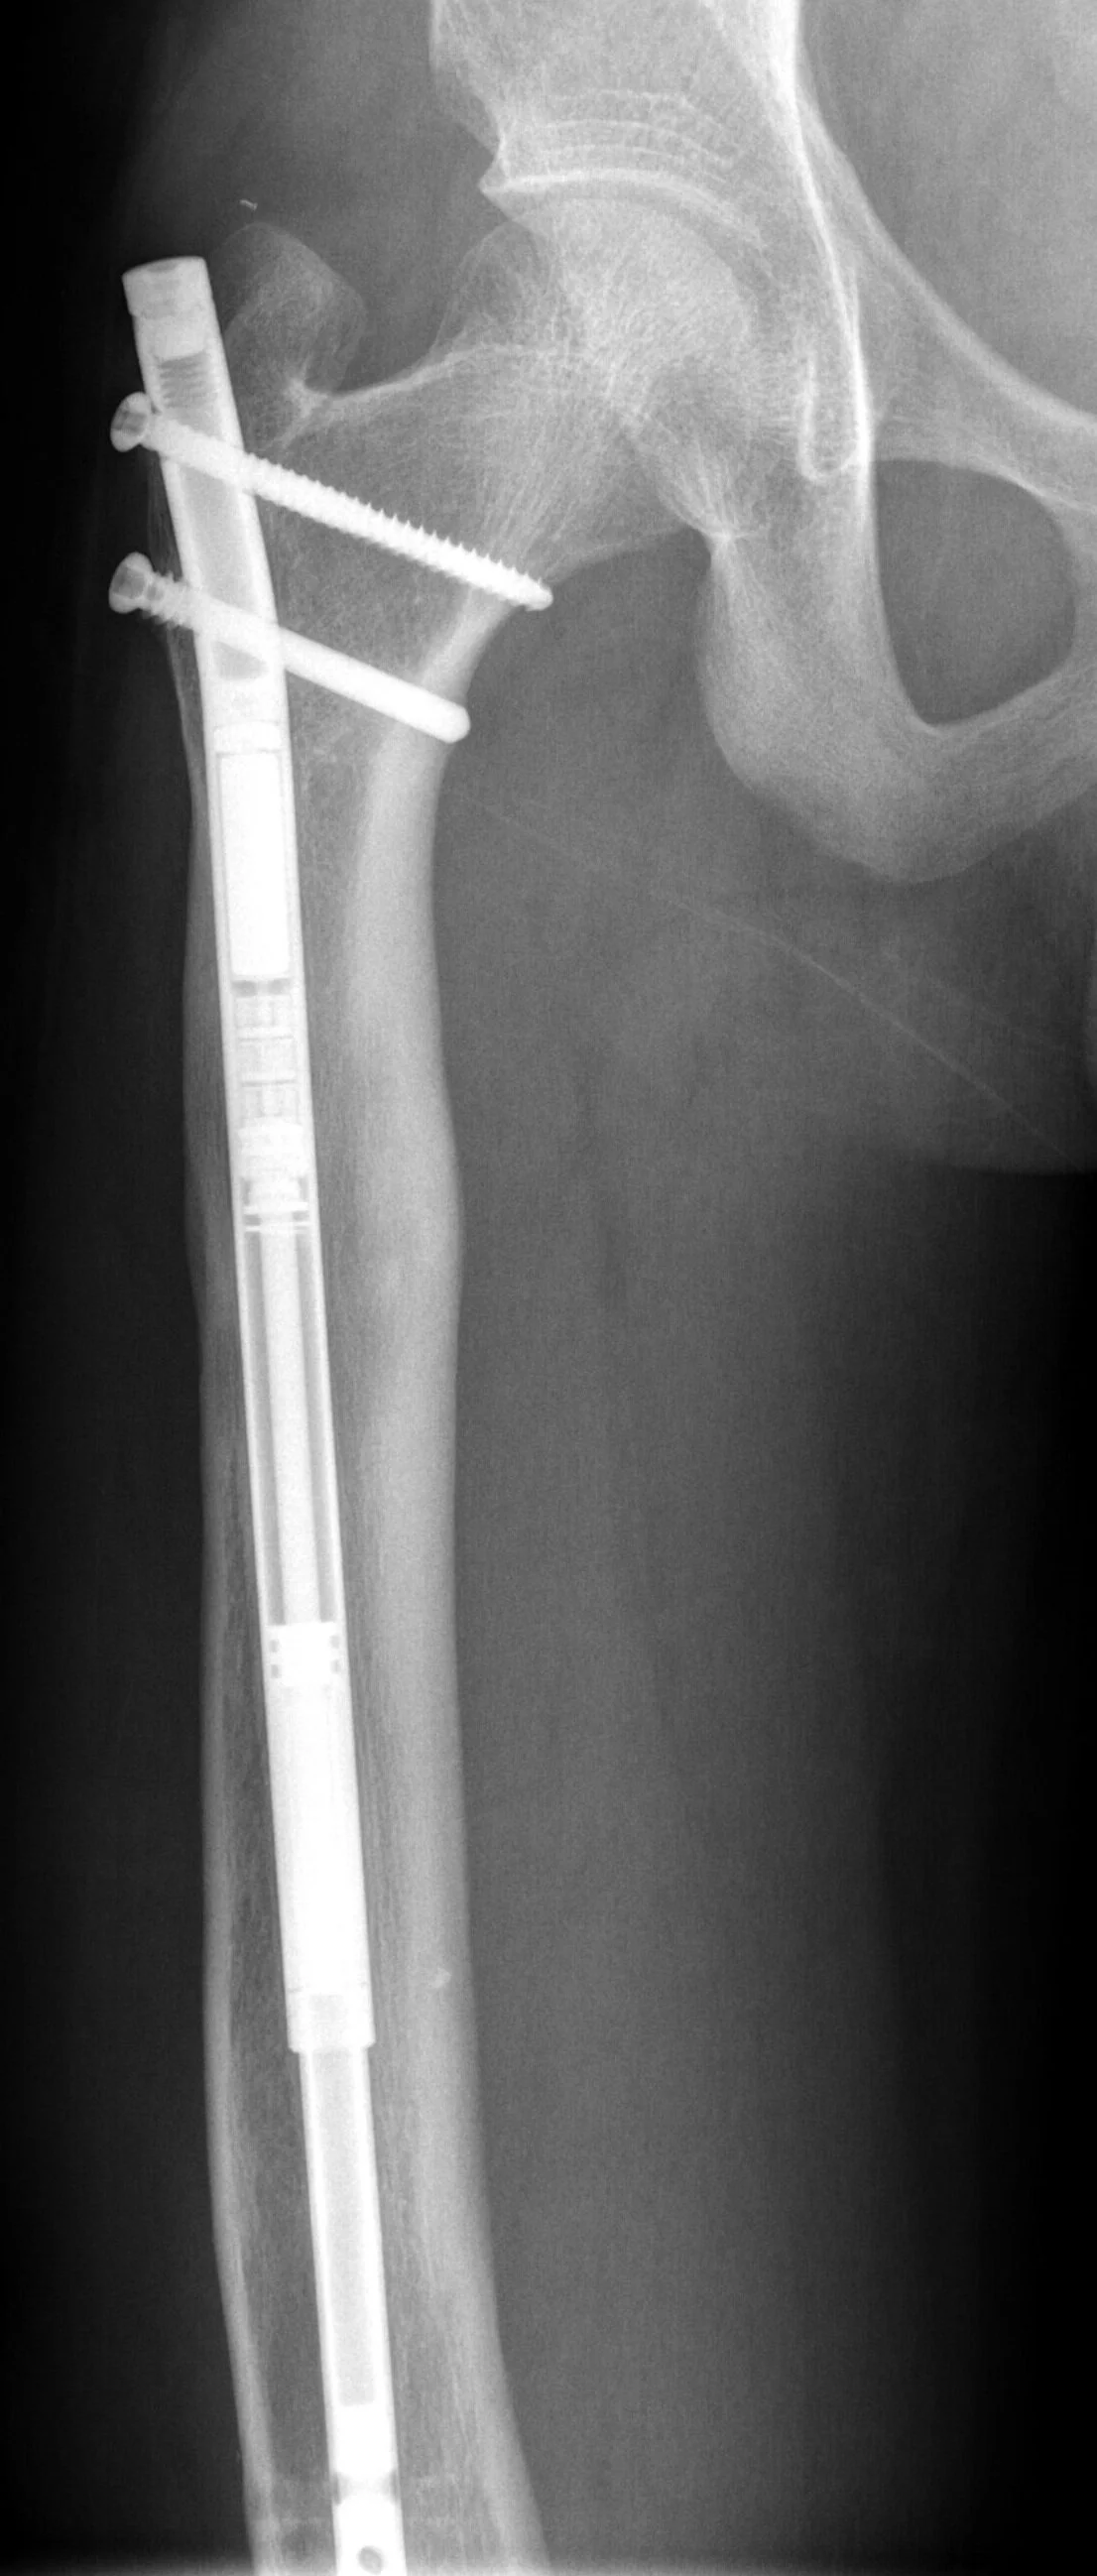

Internal Lengthening

Sometimes an internal nail and magnet can be used for lengthening . This guide covers information on the operation, aftercare, and your role in the lengthening process.